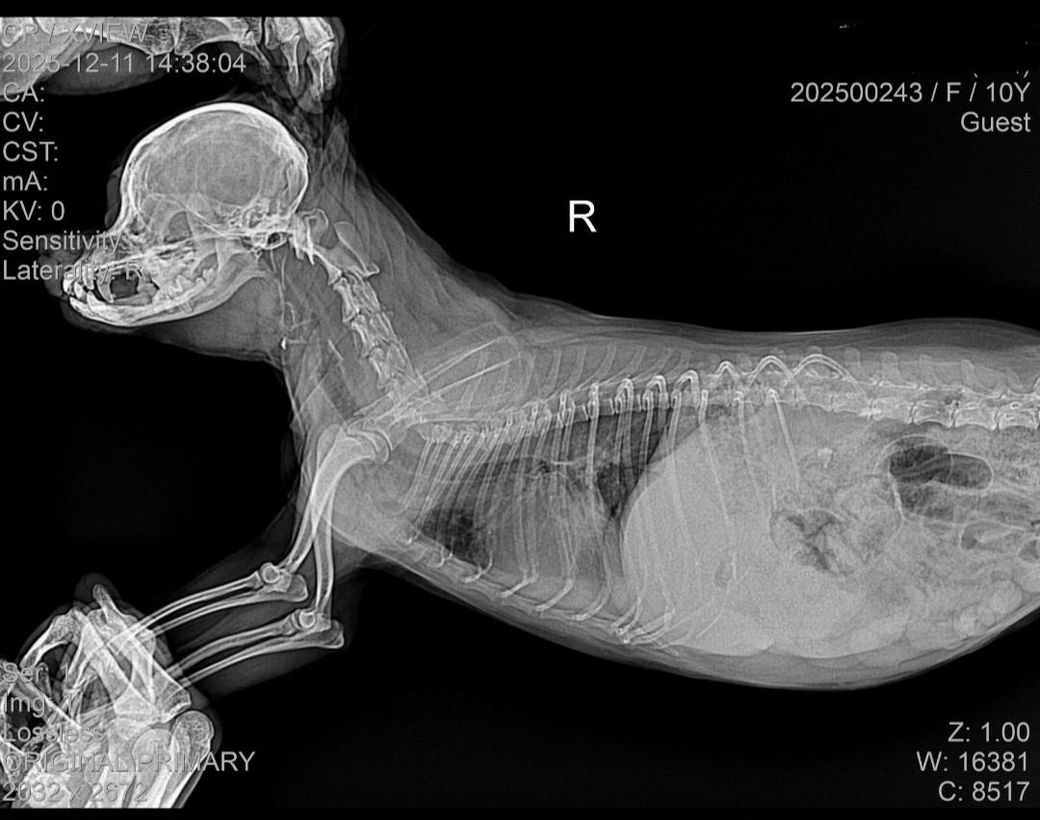

아래 사진은 입원당시 사진입니다.

양측 폐 후엽, 그리고 덧엽에 걸쳐 폐 침윤 양상이 관찰되고 있어 폐수종 가능성이 높은 상태이며, 동시에 폐렴등 이차적인 이상 가능성도 고려해야 하니 주치의의 의견을 따르시기 바랍니다. 폐와 관련된 문제는 시기를 놓치면 다음단계가 질식사이기 때문에 대응은 과도한것이 부족한것보다 언제나 압도적으로 유리합니다.